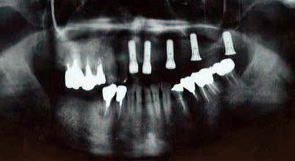

●5本のインプラントを埋入、8本の歯を回復した治療例

インプラント治療を目的として来院されました。上の一番前の歯(中切歯)2本は、歯周病のためグラグラでした。入れ歯を使用されていました。

レントゲン写真1(治療前)  入れ歯を使用していました 治療前

前歯2本を抜くのと同時にインプラント2本を入れ(抜歯即時インプラント)、他の部位にインプラント3本を入れました。また、インプラントを支える骨の量が足りないため、骨を再生し、増大させる治療(GBR法)を併用しました。時間は90分ほど、日帰りの手術です。

レントゲン写真1(治療後)  5本のインプラントを同時に入れました 手術直後

インプラントが骨とくっつくまで3ヶ月待った後、歯の型をとり、セラミックス(メタルボンド)のブリッジを装着しました。